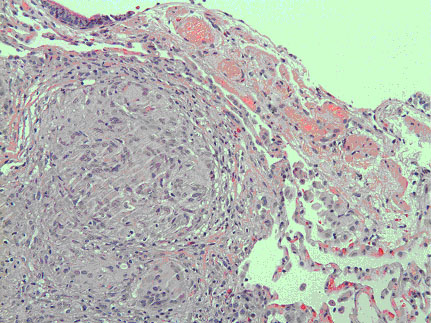

Figure 3. Slide of transbronchial biopsy showing multinucleated giant cells and epithelioid histiocytes in a granulomatous formation (Magnified 20x)